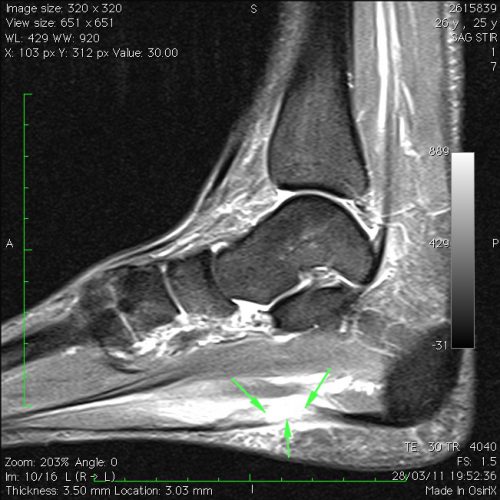

Ruptura da fascia plantar.

Atleta de 26 anos com dor súbita na região plantar do pé enquanto corria, com sensação de estalido e claudicação.

Imagem de ressonância magnética do pé (sagital STIR) com imagem de rotura da fascia plantar (setas) e hematoma perifascial.